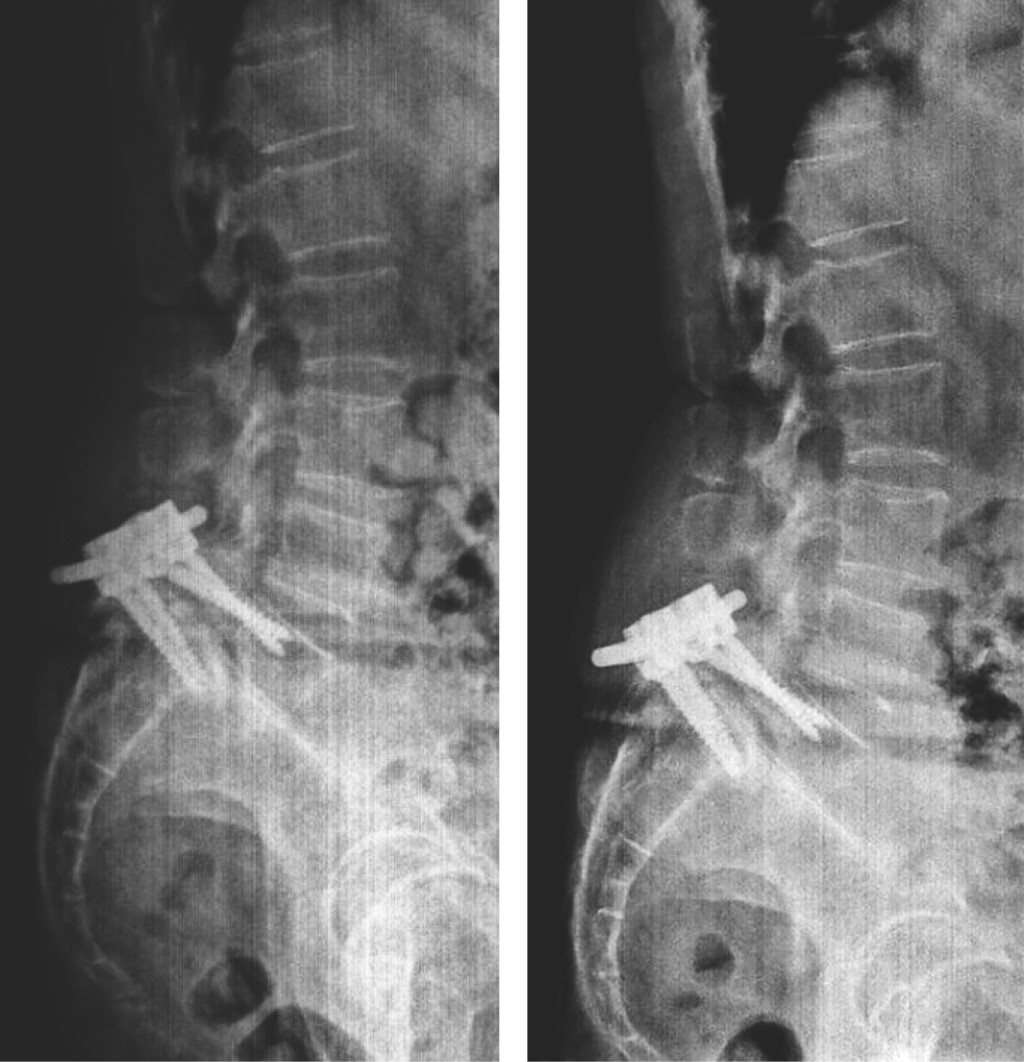

Ozone is a medical gas described since the 19th century; the ozone therapy has evolved to date in terms of its applications and its usefulness in various diseases due to its action at the molecular level and in dissimilar diseases associated with painful processes of inflammatory origin such as present in herniated discs of the spine, although the benefits of its application are currently in controversy, as well as the various complications that may occur after its application. Pneumocephalus is a complication that occurs in the background of a head injury or neurosurgery. Ozone infiltrations are used for the treatment of disc prolapse to reduce clinical symptoms. The anti-inflammatory effect of ozone is supported by its ability to oxidize compounds that contain double bonds such as arachidonic acid and prostaglandins, which are active substances with high concentrations in the inflammatory process. The appearance of pneumoencephalus and arachnoiditis chemical after epidural injection and also with ozone infiltrations is a rare complication but it has been described in recent years as a devastating post-application complication. Arachnoiditis can present as sensory and motor deficits, paresthesias, transient radicular neurological syndrome (TRNS), cauda equina syndrome, and conus medullaris. In relation to arachnoiditis, cases as severe as cauda equina syndrome after spinal anaesthesia, and more benign such as TSNR have been described, characterized by low back pain that radiates to the lower extremities, and not associated with motor deficits. neither sensitive, nor sphincter incontinence, which appears in the first 24 hours, which can last several days, and which resolves without neurological sequelae. Understanding the pathophysiology is important to assess and diagnose this type of neurological complications, especially in patients with disc disease who have undergone this type of treatment. The purpose of this report is to present the case of a patient with disc disease with the presence of radiculopathy who underwent infiltration by ozone therapy, who immediately presented complications such as pneumoencephalus and chemical arachnoiditis that led her to remain hospitalized in intensive care and present cauda equina syndrome.REFERENCES